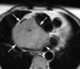

Cardiac tumor

Primary tumors of the heart are extremely rare tumors that arise from the normal tissues that make up the heart. This is in contrast to secondary tumors of the heart, which are typically either metastatic from another part of the body, or infiltrate the heart via direct extension from the surrounding tissues. [Source: Wikipedia ]